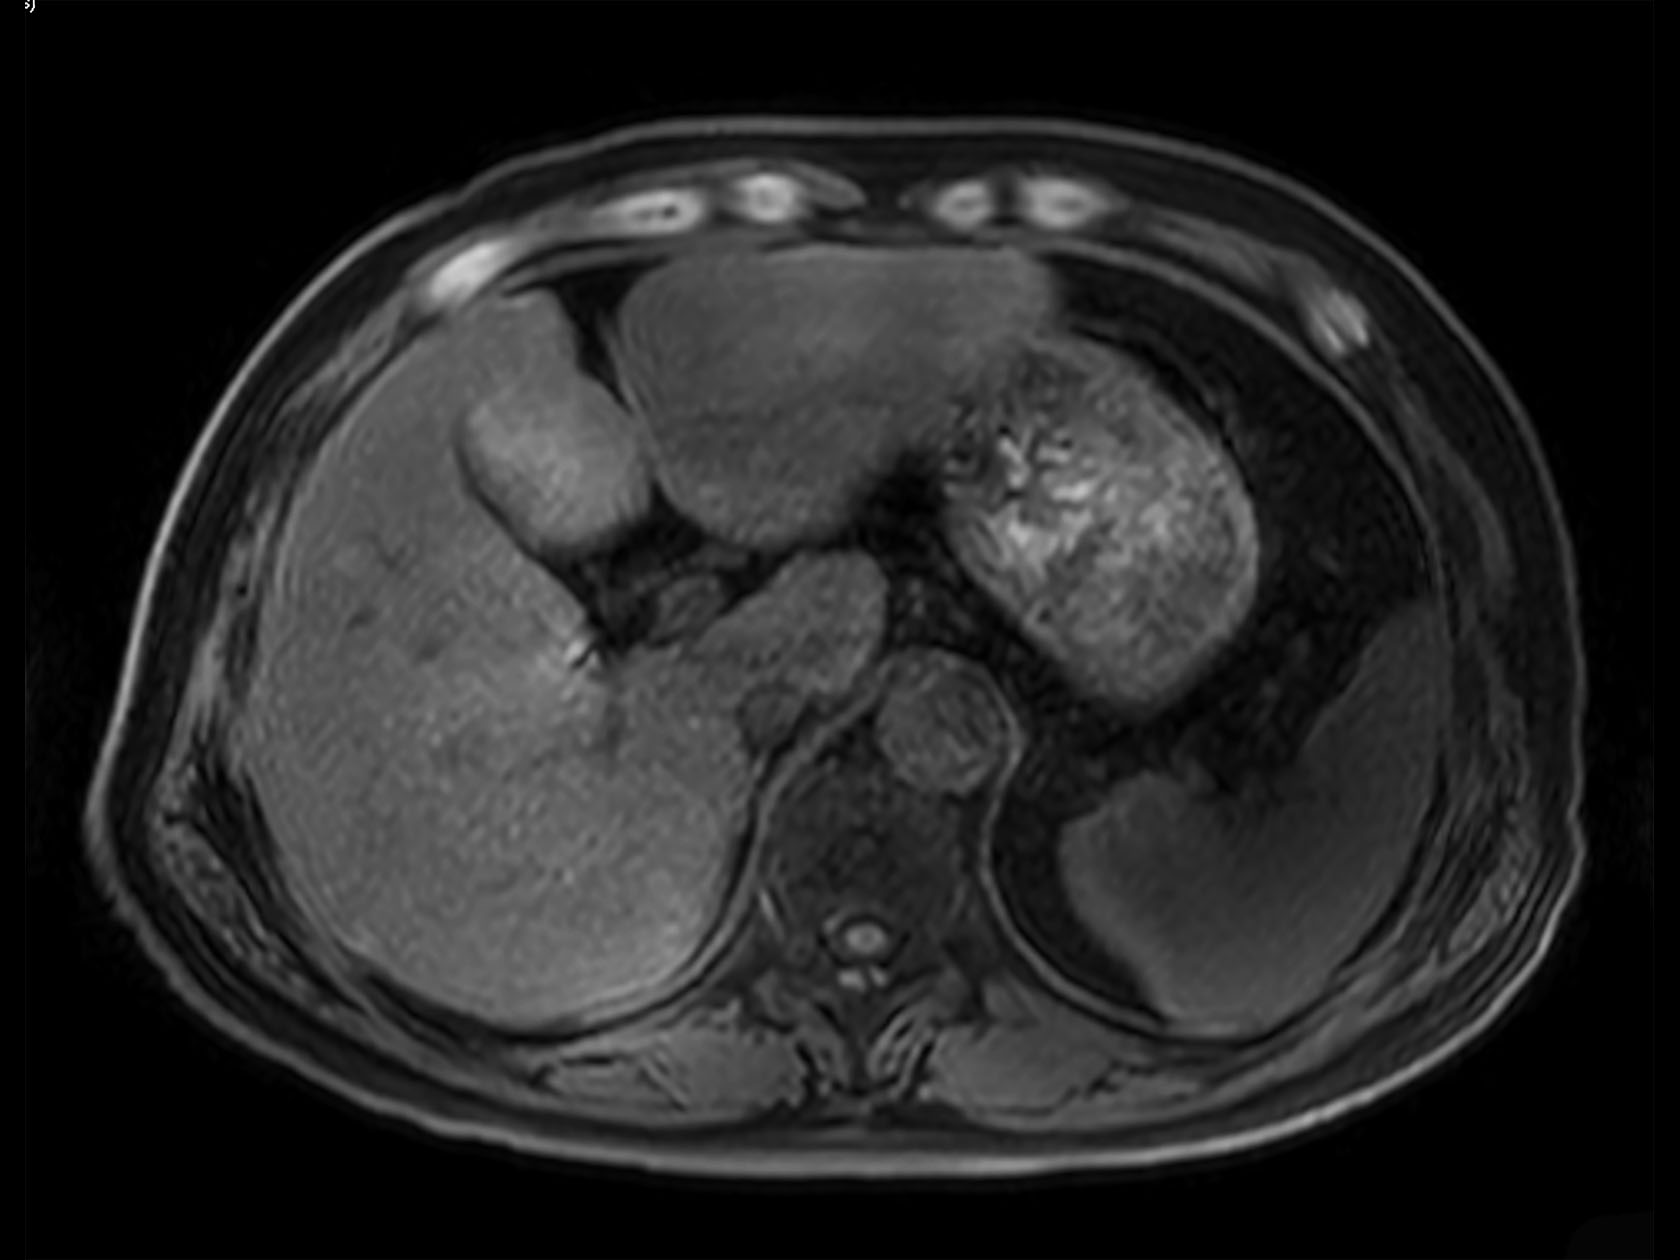

Axial mDIXON XD FFE (Water only)

Axial mDIXON XD FFE (In Phase)

Axial mDIXON XD FFE (Out Phase)

Axial mDIXON XD FFE (Fat only)

Axial 3D VANE XD (Water only)

Axial 3D VANE XD (In Phase)

Axial 3D VANE XD (Out Phase)

Axial 3D VANE XD (Fat only)